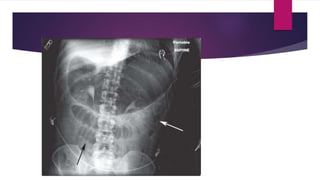

 Abdominal x ray – erect- ; multiple air fluid level

 abdominal xray - supine ; jejunanum –conniventose

; ileum- featureless

colon-haustral fold

X ray finding – volvulus

 Coffee bean appearance

investigations  Abdominal xray – erect- ; multiple air fluid level  abdominal xray - supine ; jejunanum –conniventose ; ileum- featureless colon-haustral fold CECT ABDOMEN

X ray finding– volvulus  Coffee bean appearance